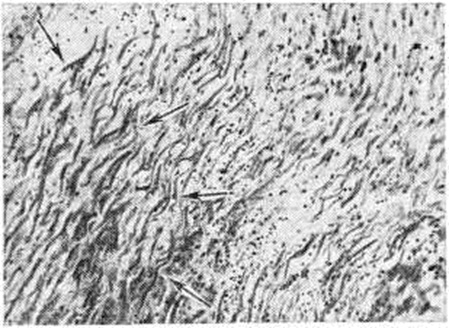

Рис. 2.

Микропрепарат миокарда: стрелками указаны мышечные контрактуры; окраска гематоксилин-эозином; × 200.